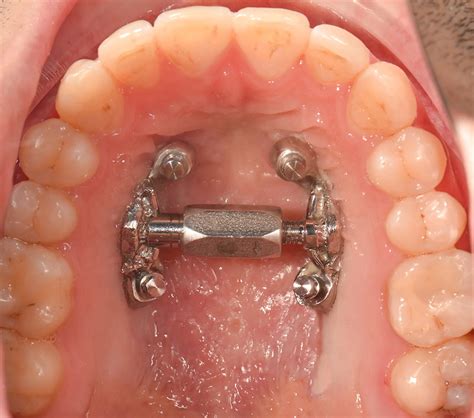

Expansor fijo con bandas (tipo Hyrax)

Es el más común en ortodoncia infantil. Consiste en una estructura metálica con un tornillo central (tipo Hyrax o similar) que se cimenta a las muelas mediante bandas metálicas. Permanece fijo 24 horas al día, lo que garantiza que la expansión es continua y no depende de la colaboración del paciente. Es ideal para expansiones significativas y para niños en dentición mixta o permanente temprana. Ventaja: muy efectivo y no requiere que el niño se acuerde de ponerlo.

Expansor asistido por microtornillos (MARPE)

Es una variante para pacientes más mayores (adolescentes tardíos o adultos jóvenes). MARPE son las siglas en inglés de Expansión Palatal Rápida Asistida con Miniscrews. En este diseño, el expansor incorpora 4 pequeños tornillos de titanio que se anclan directamente al paladar, permitiendo aplicar las fuerzas necesarias para expandir el maxilar sin tener que aplicar fuerzas en los dientes del paciente.